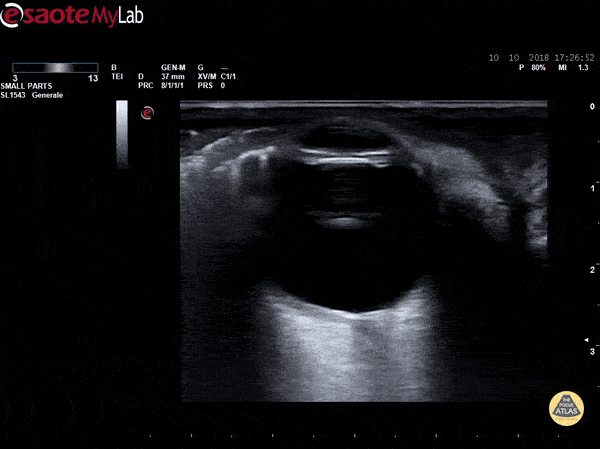

Eyelid subcutaneous emphysema detected on US ocular scan Dr. Marco Garrone